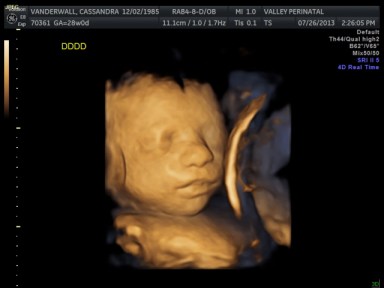

All of their organs (kidneys, bladders, hearts, brains, stomachs) look great and are also appropriate sizes. The blood flow to Elle has improved and has stabilized. All heart rates remain within normal limits, and are often on the higher side, which is probably because they just can’t sit still. We are truly excited to meet our little wiggle worms!